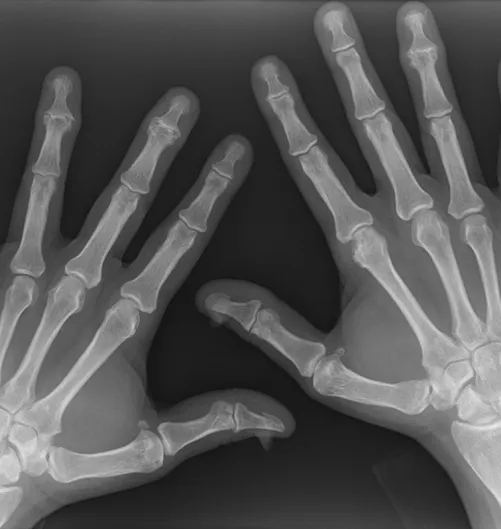

X-ray of structural damage3

Case courtesy of Alborz Jahangiri, Radiopaedia.org. rID: 46484. For illustrative purposes only. Not an actual BIMZELX patient.

Structural damage progression in the hands, wrists, and feet was assessed on plain radiographs using the van der Heijde modified Total Sharp Score (vdHmTSS).

At Year 2, no progression was defined as a change from baseline in vdHmTSS of ≤0.5 and was observed in 282/335 patients.